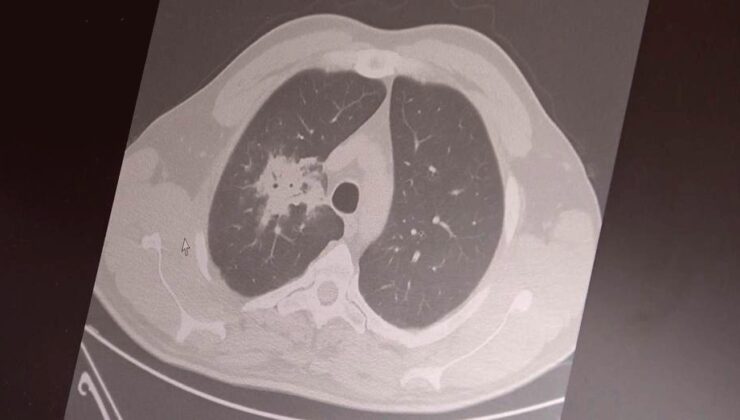

Elektronik Sigara: 20 Yıllık Süre Doldu, Kanser Riski Ortada

Göğüs Hastalıkları Uzmanı Prof. Dr. Şevket Özkaya, elektronik sigaraların 20-30 yıllık kullanım süresinin dolduğunu ve kanser riskini artırdığını söyledi. 100'den fazla çalışmanın incelendiği belirtildi.

Göğüs Hastalıkları Uzmanı Prof. Dr. Şevket Özkaya, elektronik sigaraların sağlık üzerindeki etkilerine dair önemli uyarılarda bulundu. 2000’li yılların başında daha masum bir alternatif olarak sunulan elektronik sigaraların, beklenen 20-30 yıllık kullanım süresinin dolmasıyla birlikte kanser riskini artırdığına dair bilimsel verilerin gün yüzüne çıktığını belirtti. Özkaya, bu ürünlerin başlangıçta daha az kokulu ve daha temiz bir seçenek olarak pazarlanmasının ardından milyonlarca kişi tarafından benimsendiğini hatırlattı.

Yıllardır kullanıcıların “zararlı mı, sigaraya göre daha mı az zararlı” sorularına karşılık verdiklerini ifade eden Özkaya, “Bu tür ürünlerin zararlarının en az 20-30 yıllık kullanım sonrası ortaya çıkacağını öngörmüştük. Bu süre tamamlandı ve bilimsel veriler artık elimizde” dedi.

100’den fazla bilimsel çalışmanın incelendiğini aktaran Özkaya, elektronik sigaraların özellikle akciğer ve ağız bölgelerinde kanser riskini artırdığına dair güçlü kanıtlar bulunduğunu vurguladı. Uzun vadeli sonuçların henüz tam olarak netleşmemiş olsa da, mevcut erken uyarıların ciddi boyutlarda olduğunu belirtti. İnsan, hayvan ve laboratuvar verilerini içeren araştırmaların değerlendirildiğini söyleyen Özkaya, elektronik sigaraların içerdiği kimyasalların hücre düzeyinde hasara yol açtığının tespit edildiğini kaydetti.

Elektronik sigaraların, kanser gelişiminde kritik rol oynayan DNA hasarı, oksidatif stres ve kronik iltihaplanma gibi üç temel mekanizmayı tetiklediğini belirten Özkaya, “Bu üç faktörün doğrudan kanser oluşumuna neden olduğu biliniyor” diye konuştu.

2024 yılında yayımlanan bir araştırmaya göre, hem geleneksel sigara hem de elektronik sigara kullanan bireylerde akciğer kanseri riskinin, yalnızca sigara içenlere kıyasla dört kat daha fazla olduğu bildirildi.

Özellikle gençler arasındaki elektronik sigara kullanımının yaygınlaştığına dikkat çeken Özkaya, lise çağındaki bireylerde ve 40 yaş altı gruplarda kullanım oranlarının arttığını vurguladı. Elektronik sigara ile başlayan gençlerin ilerleyen dönemlerde normal sigaraya yönelme olasılığının daha yüksek olduğunu belirtti. Özkaya, erken bilimsel bulguların göz ardı edilmemesi gerektiğini yineleyerek, “Bugün gerekli önlemler alınmazsa, gelecekte çok daha büyük bir halk sağlığı sorunu ile karşılaşabiliriz” uyarısında bulundu.